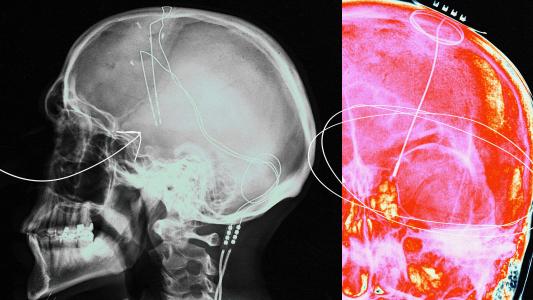

A new study led by researchers from the Massachusetts General Research Institute, however, may have discovered an important clue in the thalamus, specifically a part called the “thalamic reticular nucleus.” It’s a relay center that sends data to the outermost layers of the brain through a network of nerve fibers, and it plays pivotal roles in the sleep-wake cycle, directing attention, and how we process sensory information, like pain.